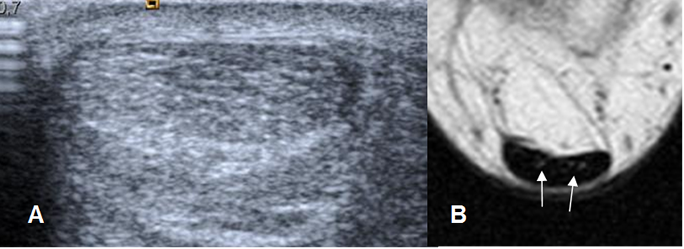

En ecografía, los ligamentos son estructuras lineales e hipoecoicas, con un espesor menor a 2 mm. (4). (Fig 9 y 15).

Fig 9. Ligamentos peroneoastragalinos normales en ecografía.

Ligamento peroneoastragalino anterior en A y peroneoastragalino posterior en B.